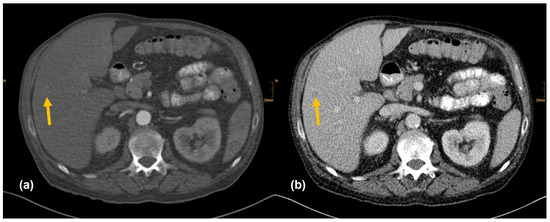

Figure 4. Hepatocelluar carcinoma in the right lobe (arrow). (a) Low contrast enhancement in the arterial phase. (b) Washout in the venous phase. All readers did not report the nodule whether clinical information was provided (Seizure after alcohol withdrawal. Known liver cirrhosis and hepatosplenomegaly.).

There are several reasons why tumors and metastases could be missed by radiologists. Firstly, the interpretation of oncological CT data sets is challenging; often multiple abnormalities are present in a single patient. Lesions may be benign and not always malignant. Therefore, findings could be undercalled and misinterpreted as benign (e.g., Figure 2) [1]. Findings may also be too small to be classified as malignant or may be overlooked (e.g., Figure 4). Additionally, findings, particularly of the lung, could be consistent with a postinflammatory benign aetiology due to configuration and subpleural location (e.g., Figure 5) [46]. Secondly, the so-called satisfaction of search represents another possible influence on the detection rate of malignant lesions. Satisfaction of search represents an interference of a radiological finding with the detection of further abnormalities [1,47]. Radiological image interpretation often follows a fixed procedure. Thus, as soon as a finding (mostly the primary tumor) is made, further lesions as metastases may be missed. This may explain the lower rate of true positive metastatic findings. Further reasons for missed metastatic lesions can be assumed. Metastases are often small, not reliably distinguishable from benign lesions and therefore an unequivocal diagnosis is often impossible without follow-up imaging or complementary procedures such as MRI, hybrid imaging, or biopsy. Moreover, imaging criteria for lymphogenous metastases are often controversial, an accurate identification is challenging. In the past, a short axis diameter of 1 cm was used as the cut-off value for enlarged, malignancy-susceptible lymph nodes [1]. Recent studies suggest different parameters for various anatomic regions, such as 6 mm for retrocrural or 8–10 mm for pelvic lymph nodes. However, enlarged lymph nodes are not always malignant. They also could have an inflammatory aetiology or normal-sized lymph nodes may have tumor involvement [48]. Of course, there are numerous cases in the present study that had been solved correctly. Figure 3 shows an example of a pancreatic carcinoma correctly diagnosed by all three radiologists irrespective of clinical information.